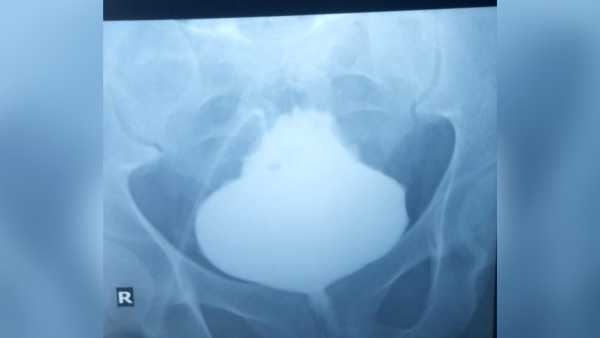

The treatment: The medical team created a tiny, keyhole opening in the patient’s abdomen that permitted the escape of the confined nitrogen gas. They then put in place a laparoscope — a slim tube containing a camera — through the keyhole and into the stomach so as to locate and repair the rupture. Finally, using some fatty tissue from another part of the patient’s abdominal area, they stitched up and sealed the 1.2-inch-wide (3 centimeters) gap.